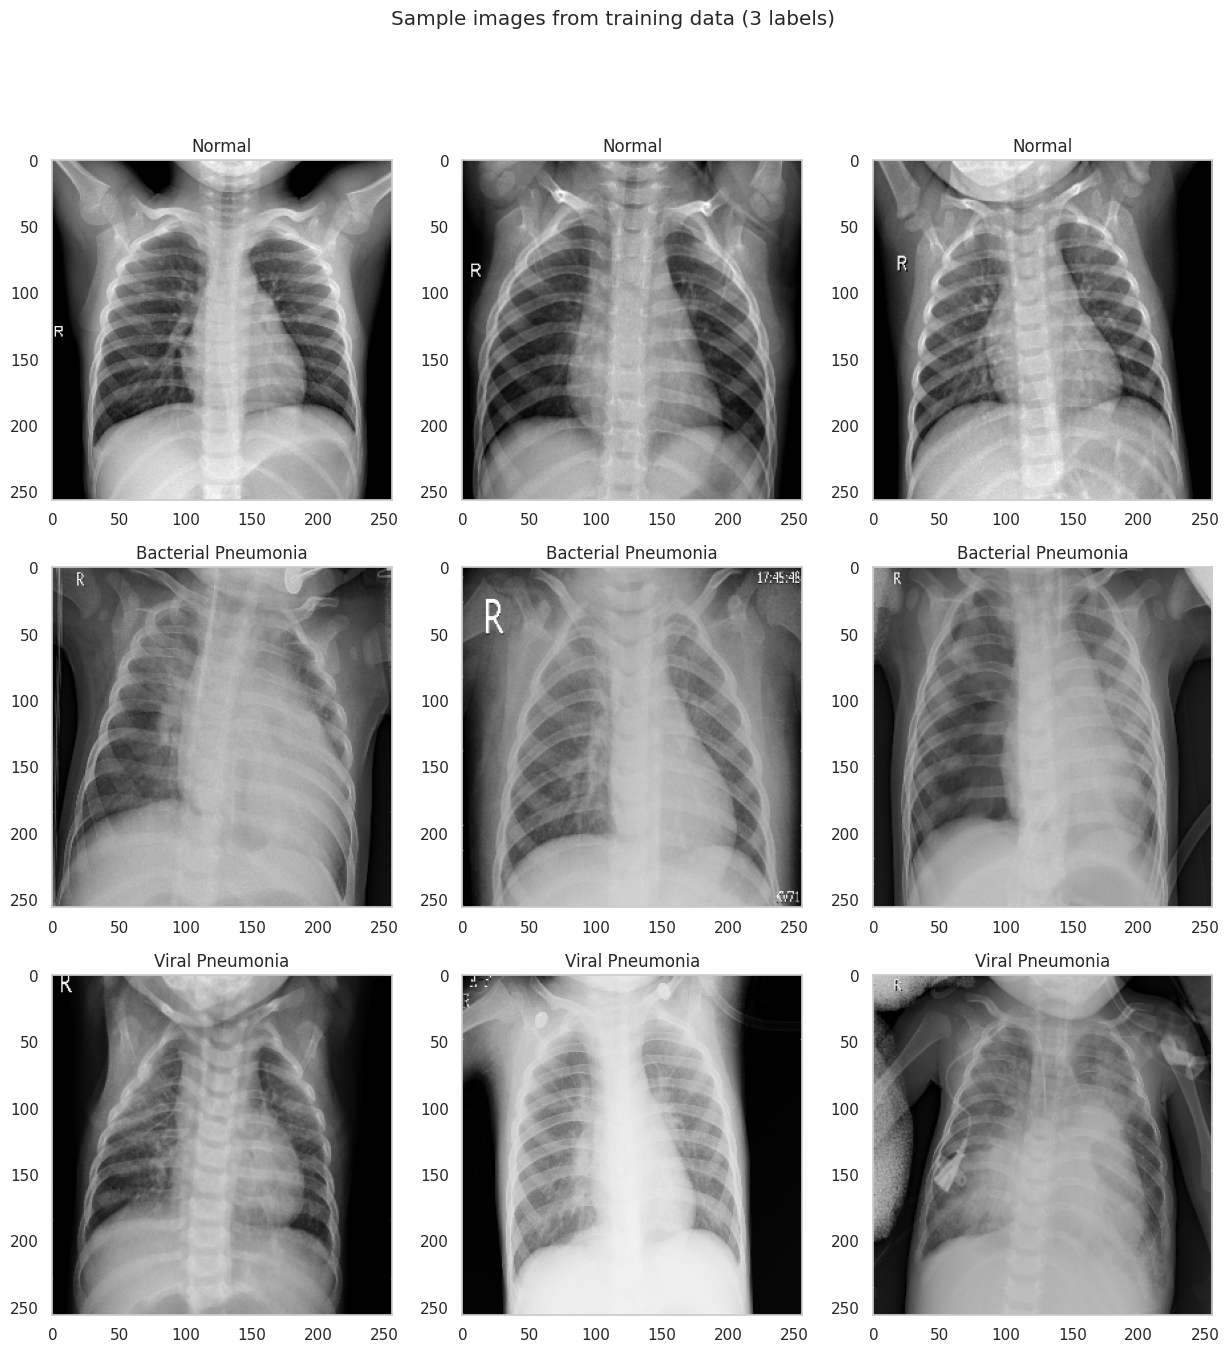

The dataset consists of pediatric chest X-ray images from Guangzhou Women and Children’s Medical Center, split into three classes: normal, bacterial pneumonia, and viral pneumonia. For our classification task we merge the two pneumonia subtypes into a single positive class, giving us a binary problem.

2.1 Visual Differences

Even to a non-expert eye, the two classes look different. Normal X-rays tend to be sharper with clearly delineated lung fields, visible rib structure, and a well-defined cardiac silhouette. Pneumonia images often show diffuse haziness or localized opacities that obscure parts of the lung, making it harder to distinguish the heart from the surrounding tissue.